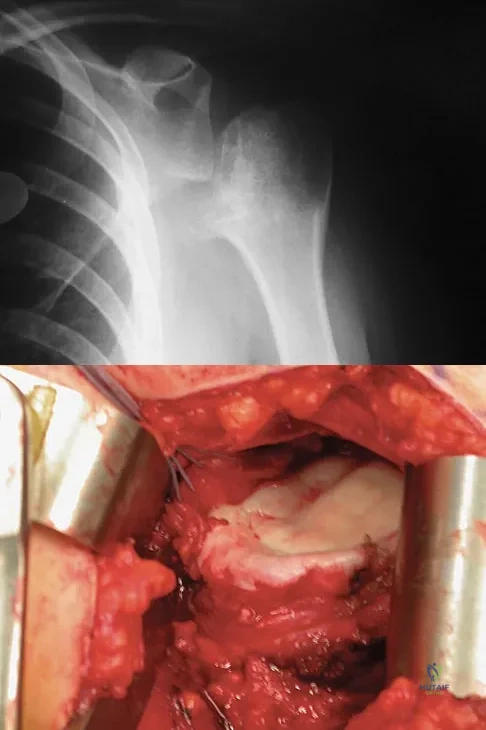

A 28-year-old man sustained a shoulder dislocation 2 years ago. It remained dislocated for 3 weeks and required an open reduction. He now reports constant pain and has only 60 degrees of forward elevation and 10 degrees of external rotation. He desires to return to some sporting activities. An AP radiograph and intraoperative photograph (a view of the humeral head through a deltopectoral approach) are shown in Figures 31a and 31b. What is the best treatment option to decrease pain and improve function?

Explanation